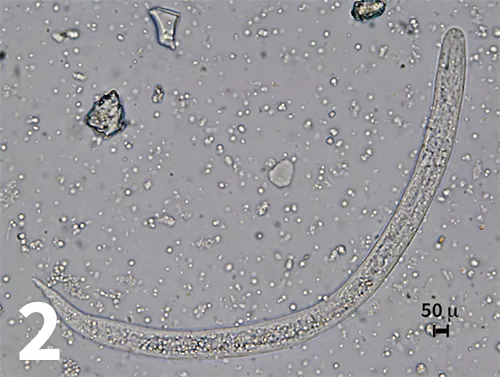

Figure 2. Dead and degenerating first-stage larva recovered by fecal sedimentation. Larva is about 245 microns in length and has a bluntly rounded anterior end (original magnification 40× objective).

A fecal sedimentation test was then performed, and a Baermann examination was set up in an attempt to obtain undamaged larvae. All larvae recovered on sedimentation were dead and too degenerated to identify. The larvae were 235 to 245 microns in length, and the anterior end was bluntly rounded (Figure 2). The results of the Baermann examination obtained the following day were negative. CBC and serum chemistry profile were within normal limits. Thoracic radiographs revealed a diffuse pulmonary bronchointerstitial pattern.